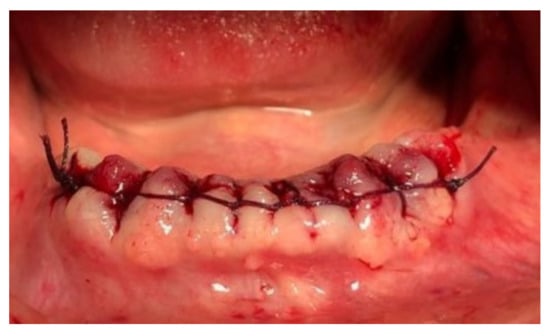

| Tissue colour: | All tissues pink |

| Granulation tissue: | None | |

| Incision margin: | No connective tissue exposed | |

| Suppuration: | None |

| 3 days | 2.15 ± 0.67 | 2; 0 | 1.75 ± 0.44 | 2; 0.25 | 0.038 |

| 7 days | 3 ± 0.73 | 3; 0.5 | 2.3 ± 0.47 | 2; 1 | 0.002 |

| 14 days | 4.2 ± 0.52 | 4; 0.25 | 3.8 ± 0.77 | 4; 1 | 0.074 |

| 28 days | 4.95 ± 0.22 | 5; 0 | 4.75 ± 0.44 | 5; 0.25 | 0.080 |

| Significance | 0.0001 | 0.0001 | |||